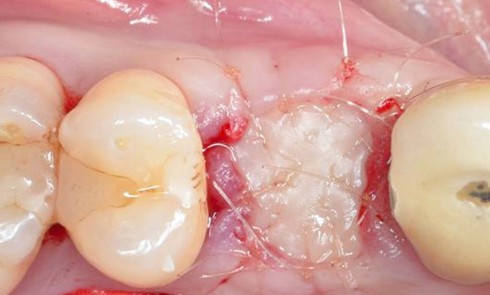

Nous proposons de retirer la couronne et le pilier implantaire, d’effectuer une greffe de tissu conjonctif enfouie afin d’améliorer le volume du tissu kératinisé péri-implantaire [5] et de procéder à la pose d’une couronne provisoire transvissée (fig. 3a à h).